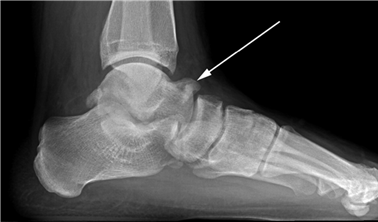

Weight-bearing anteroposterior (AP), lateral, and sesamoid axial radiographs are mandatory. On the AP view, the surgeon measures the Hallux Valgus Angle (HVA, normal < 15°), the Intermetatarsal Angle (IMA, normal < 9°), and the Distal Metatarsal Articular Angle (DMAA). The lateral view is scrutinized for Meary's angle (talo-first metatarsal angle) to identify midfoot collapse, as well as the presence of dorsal osteophytes indicative of hallux rigidus. The sesamoid axial view is critical for assessing the degree of sesamoid subluxation and the integrity of the crista.

Avascular necrosis of the metatarsal head is a devastating complication primarily associated with distal osteotomies. It presents with insidious onset of pain, swelling, and eventual radiographic collapse of the articular surface. Prevention is paramount and relies on preserving the plantar-lateral soft tissue attachments during the lateral release. If symptomatic AVN occurs and progresses to joint destruction, the definitive salvage procedure is a first MTP arthrodesis, often requiring structural bone grafting to restore metatarsal length.